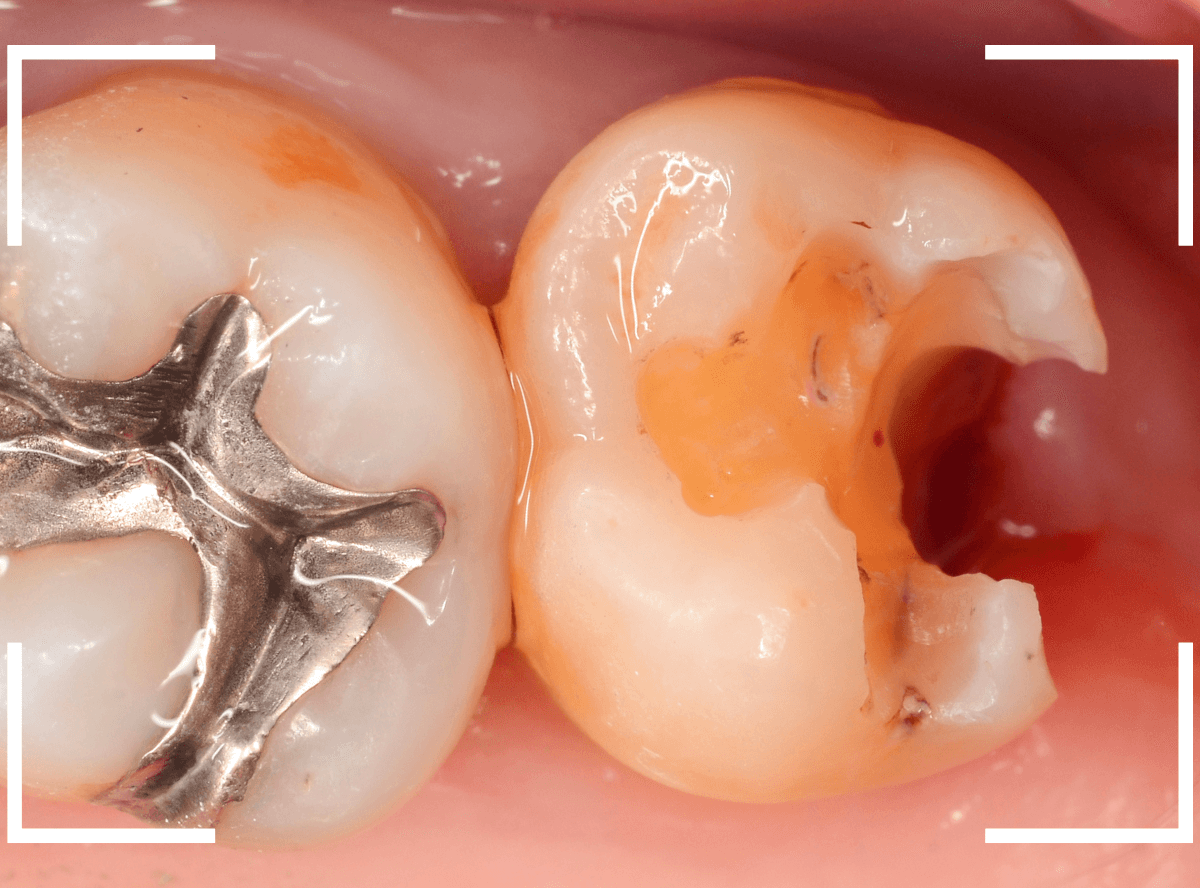

Case.8 治療を中断して、つめものが取れてさらに虫歯が進行したケース

こちらも、前のケースの方と同じように、治療中断後、つめものが取れて長期間放置してしまった患者さんのケースです。

しみるなどの症状が現れたので、来院に至ったようなのですが、症状が出ている場合、だいたい、虫歯は重症化している事が多いです。

レントゲン写真で確認します。

青いラインが神経、赤いラインが虫歯と思われる部分です。

前後の歯まで、虫歯が広く進行しているのが想定できます。

虫歯の治療を開始すると、すぐに深めの虫歯が出てきました。

神経に近い部分まで虫歯が進行していますので、慎重に虫歯を除去します。

全ての虫歯を除去しました。

前後の歯にまで虫歯が広く進行していました。